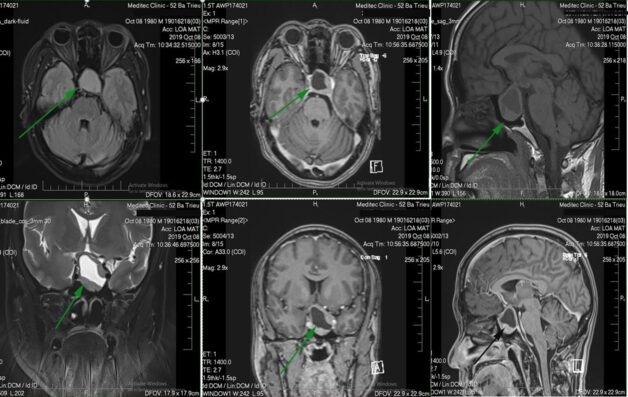

MRI có thể chụp ảnh ở nhiều mặt phẳng (sagittal, axial và coronal), cung cấp một cái nhìn toàn diện về vùng tuyến yên. Khả năng hình dung các cấu trúc từ các góc độ khác nhau giúp chẩn đoán chính xác.